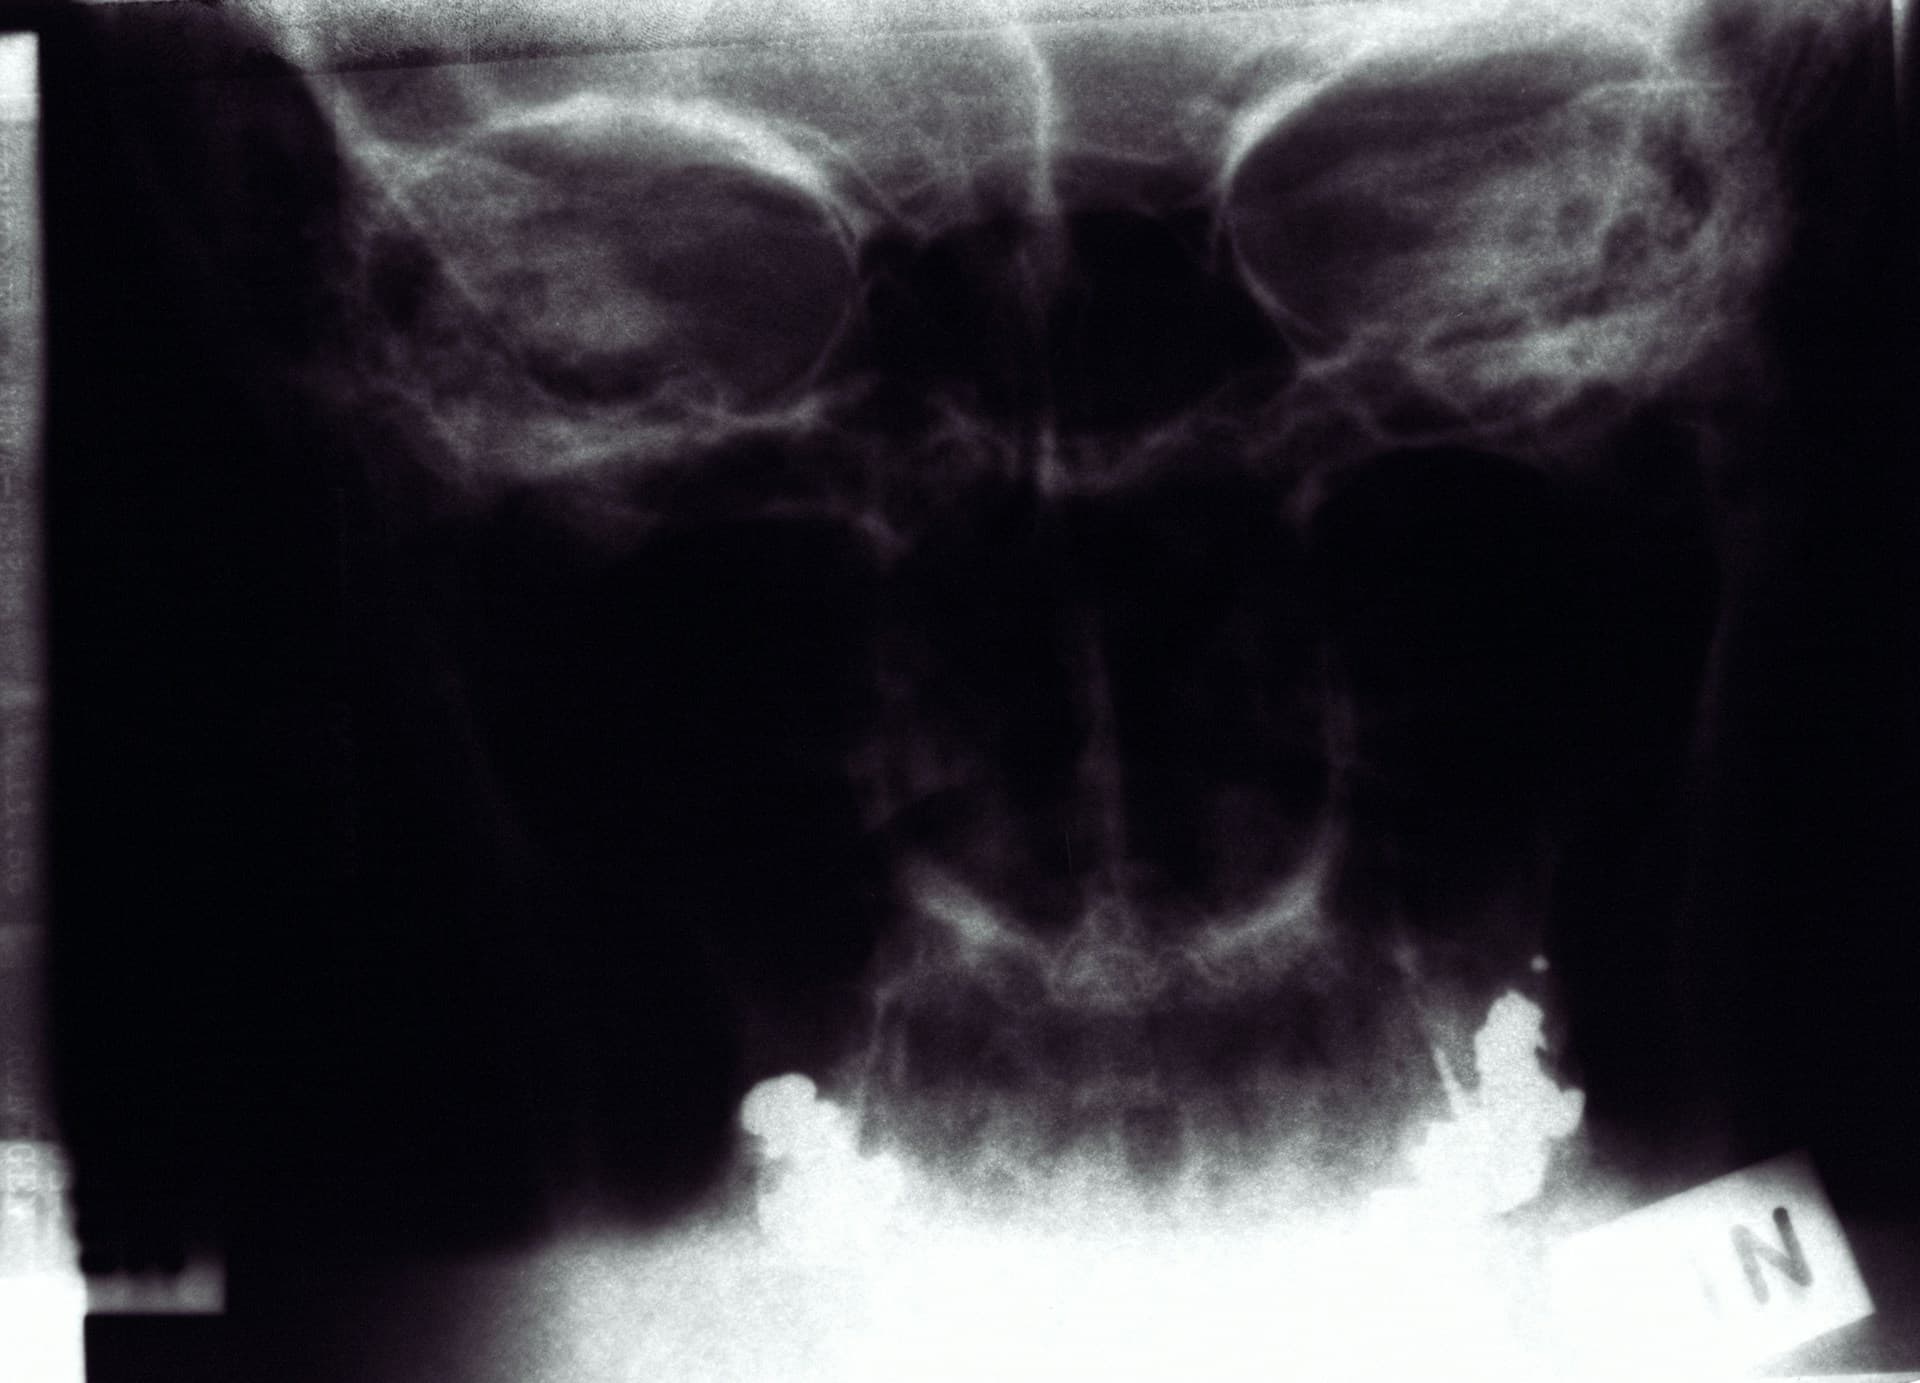

Со временем недостаток кальция может вызвать остеопению – снижение минеральной плотности костей. А остеопения может привести к остеопорозу, т.е. истончению костей. Люди становятся уязвимыми для переломов, а также страдают отболи и проблем с осанкой.

Могут пройти годы, прежде чем у человека разовьется остеопороз и другие осложнения дефицита кальция. Но лечение остеопороза — это дорогостоящий процесс, требующий госпитализаций, хирургического вмешательства и длительной реабилитации.

Поэтому так важна профилактика дефицита кальция как способ поддержания здоровья костей и нервной системы.